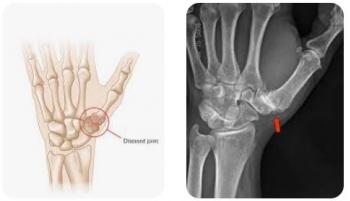

Thumb CMC arthritis is a common degenerative condition that causes pain, weakness, and reduced hand function, significantly impacting daily activities such as gripping, pinching, and fine motor tasks. When conservative treatments fail to provide adequate symptom relief, surgical intervention may be required. CMC arthroplasty is indicated to relieve pain, restore joint mechanics, and improve functional outcomes, allowing patients to regain hand strength, mobility, and quality of life.